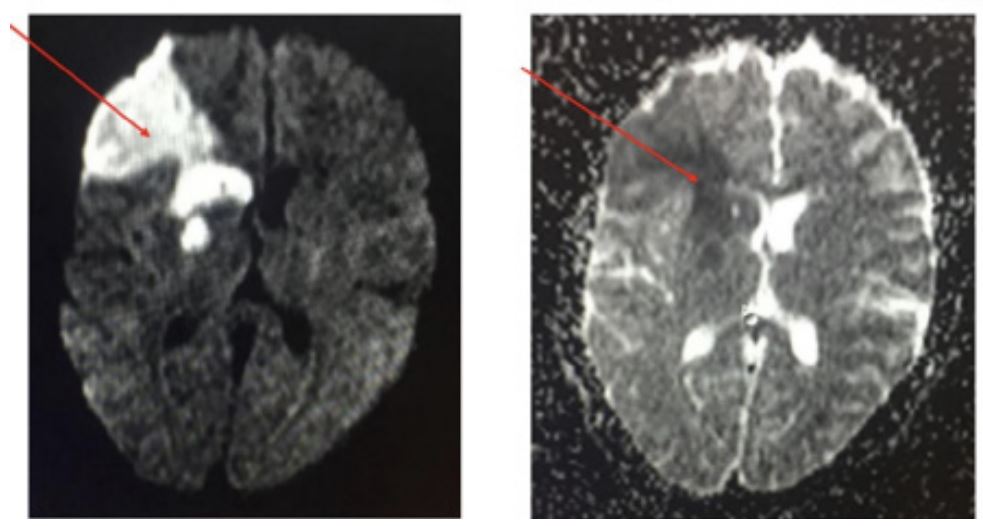

MRI brain done along with MR Angiography-Showed a T2/FLAIR hyperintensity with diffusion restriction in DWI noted right frontal and right gangliocapsular region (Figure 1 marked in red arrow) along with partially thrombosed aneurysm of size 1.8 cm x 1.7 cm arising from M2 segment of Right middle cerebral artery (Figures 2 and 3). Then patient undergone 4 Vessel Doppler of neck and echocardiography, as it showed no evidence of thrombi. Then Serum homocysteine, serum ANA. APLA profile done. USG abdomen screening done for ADPKD. All investigations are within normal limits. So final diagnosis Spontaneous Thrombosis of Unruptured intracranial aneurysm causing acute infarct presenting as isolated Left UMN facial palsy. Neurosurgery opinion obtained as it was spontaneously thrombosed non giant intracranial aneurysm with acute infarction advised to start antiplatelet therapy and watch for any evidence of rupture. After 6-month follow-up, MRI taken aneurysm completely thrombosed and advised to continue antiplatelet therapy.

Figure 1: MRI brain done along with MR Angiography-Showed a T2/FLAIR hyperintensity with diffusion restriction in DWI noted right frontal and right gangliocapsular region (marked in red arrow).

Figure 2 & 3: MRI Along with partially thrombosed aneurysm of size 1.8 cm x 1.7 cm arising from M2 segment of right middle cerebral artery.